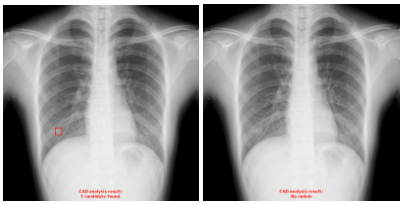

・偽陰性の改善例

旧モデルでは肋骨の重なりに隠れた肺結節候補域を検出できていなかったが,新モデルでは検出できている。(5)

※左:旧モデルによる解析結果,右:新モデルによる解析結果